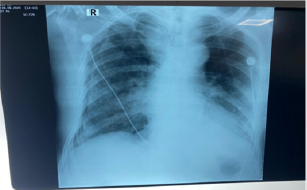

A 81 year old man presented into the emergency department of KRL Hospital Islamabad with shortness of breath and Acute Kidney Injury.According to patient’s attendant he was in unusual state of health when he developed mild burning micturition along with low grade fever which was relieved by panadol. He had shortness of breath from 02 years which progressed from MMRC grade 2 to grade 4. He also had an history of Hypertension, Ischemic Heart Disease having an Ejection Fraction 25%, along with pulmonary edema.Initially patient was maintaining O2 stats at room air but then started on O2 therapy and later on shifted to nasal cannula. He was well oriented in time and space but then he became critically ill due to multi organ involvement. He was confused, tachypnic and not following any commands(Figure 2). His blood pressure was 168/98 mm Hg where as blood sugar random measured was 140 mg/dl/. ECG showed hyper acute t wave along with prolonged PR interval. Chest examination revealed bilateral creptsupto 2/3rd of chest with mild wheeze. Ultrasound abdomen had a bilateral echogenic kidney, mild hydronephrosis along with mild intrahepatic cholestasis. Chest x-ray revealed bilateral infiltrates reticular in base and periphery along with central consolidation giving an impression of Right Pneumothorax Table 1. Since his pneumothorax was less than 30%, he was kept under observation and managed conservatively. His current line of treatment was meropenem, azithromycin, carvedilol, asprin, steroids along side with nebulization of Atem and Clenil.

Table 1: ECG showed hyper acute t wave along with prolonged PR interval.

Chest examination revealed bilateral creptsupto 2/3rd of chest with mild wheeze. Ultrasound abdomen had a bilateral echogenic kidney, mild hydronephrosis along with mild intrahepatic cholestasis